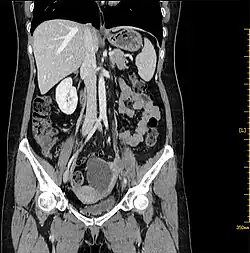

| Abdominal CT shows a 7.1 × 4.3 × 5.4 cm septal cystic, solid mass was detected on the left adnexal, and the solid components were enhanced. | |